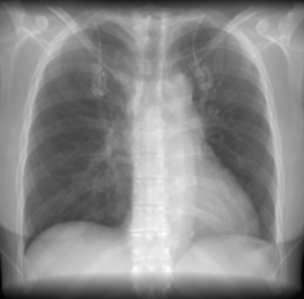

In contrast, chest X-rays (CXRs) are inexpensive and widely accessible, making them an attractive modality for opportunistic CAC risk assessment D’Ancona et al. (2023). Yet, CXRs have limited sensitivity for calcium depiction and lack standardised annotation protocols, leaving reliable ground truth labels scarce Kamel et al. (2021). Existing CXR–CT datasets are typically assembled retrospectively, requiring patients to have undergone both imaging modalities within a clinically acceptable window (often 6 months). Such dual-modality acquisitions are uncommon in routine care and, when available, can introduce temporal misalignment and label noise due to disease progression between scans. This bottleneck constrains the development of deep learning methods, and prior studies Kamel et al. (2021); D’Ancona et al. (2023); Jeong et al. (2024) remain limited in scale and generalisability.

In such data-scarce settings, an emerging strategy is to train models within surrogate domains: synthetic or simulated approximations of the target modality that preserve key imaging physics while offering abundant labels. In clinical domains, Digitally reconstructed radiographs (DRRs) are synthetic 2D projections of CT volumes that approximate real CXRs while being able to inherit precise CT-derived labels. Prior work in their generation has validated their clinical fidelity Moore et al. (2011) suggesting that DRRs may serve as a scalable proxy training domain where methodological feasibility can be established before transferring to real CXRs. Although direct transfer to real CXRs is not evaluated here, recent work has shown DRR-trained models to generalize effectively in fluoroscopic and interventional settings, supporting the plausibility of similar transferability for CAC detectionUnberath et al. (2018).

Synthetic radiographs were generated directly from CT volumes using the Siddon ray-tracing algorithm, implemented in the open-source DiffDRR framework Gopalakrishnan and Golland (2022). Siddon projection computes exact line integrals through the CT volume, avoiding interpolation artefacts and preserving small, high-density structures such as calcifications. For each scan, we simulated posterior–anterior (PA) and lateral (LA) projections under a fan-beam geometry with fixed source–detector distance (1085.6 mm) and detector width of 512 pixels at 1 mm spacing. Both PA and LA projections used identical source–detector parameters, with the LA view generated by a rotation around the cranio-caudal axis to approximate orthogonal orientation. DRRs were normalised to and resized to . This pipeline yields synthetic radiographs that approximate clinical CXRs while retaining precise CAC labels inherited from the source CTs.